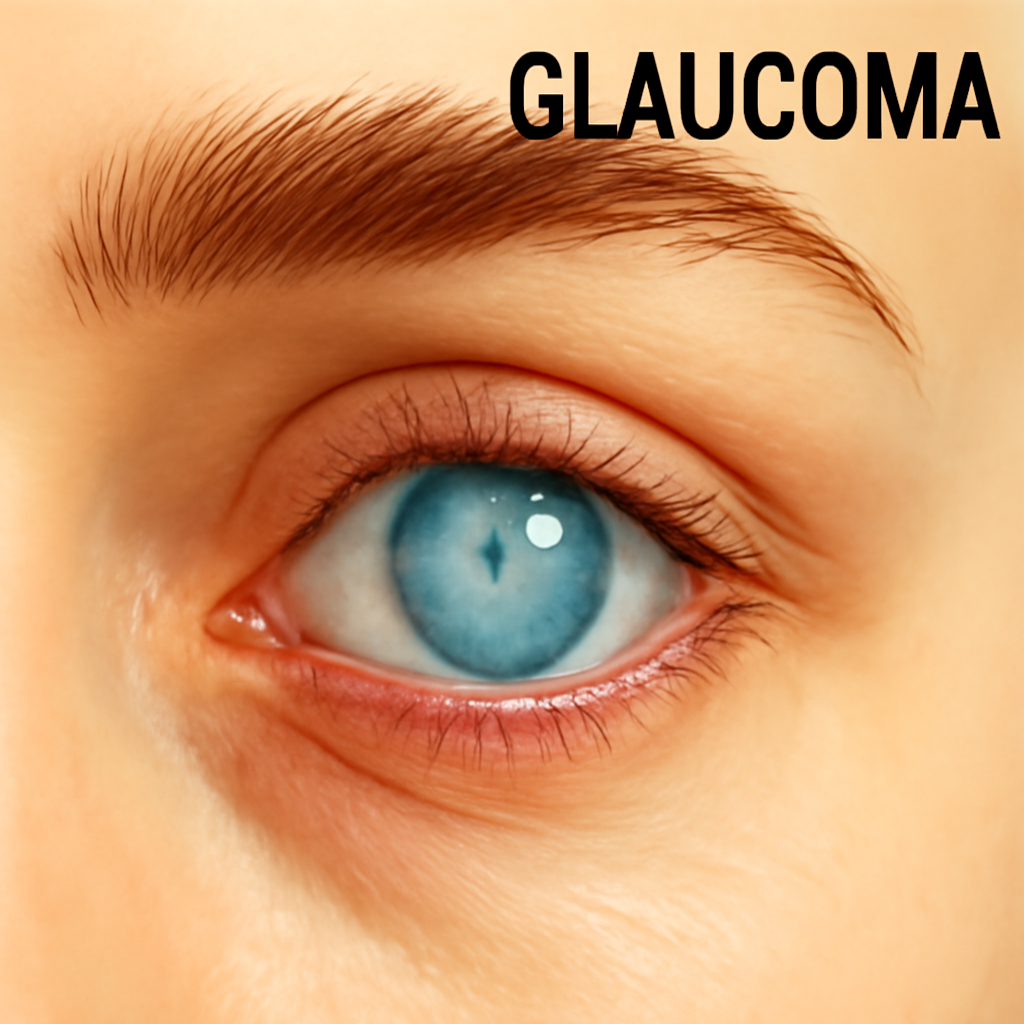

# Eyes